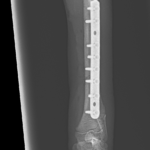

橈骨固定術 #241 Toy Poodleさん(7ヶ月齢)が室内で骨幹中央部からやや遠位の橈骨骨折をしたとの事。1.5コンベンショナルプレートで整復しました。しばらく安静が必要です。 症例カテゴリー 放射線治療整形外科軟部組織外科脳神経外科内科腫瘍外科救急・集中治療リハビリテーション科腫瘍内科内視鏡科脳神経科呼吸器外科中医・漢方猫の腎移植循環器科